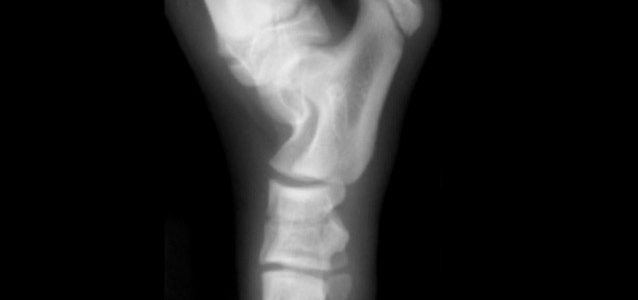

Los problemas óseos –raquitismo, hiperparatiroidismo secundario, osteofibrosis juvenil y osteodistrofia hipertrófica- son un mal relativamente frecuente que puede evitarse si se vigila convenientemente, sobre todo, la dieta del perro. Para un cachorro en crecimiento es peligroso llevar una dieta poco equilibrada o con exceso o escasez de vitaminas y minerales que pueda redundar en malformaciones óseas. Un problema que, no obstante, también puede afectar a perros adultos de raza gigante. Leer más